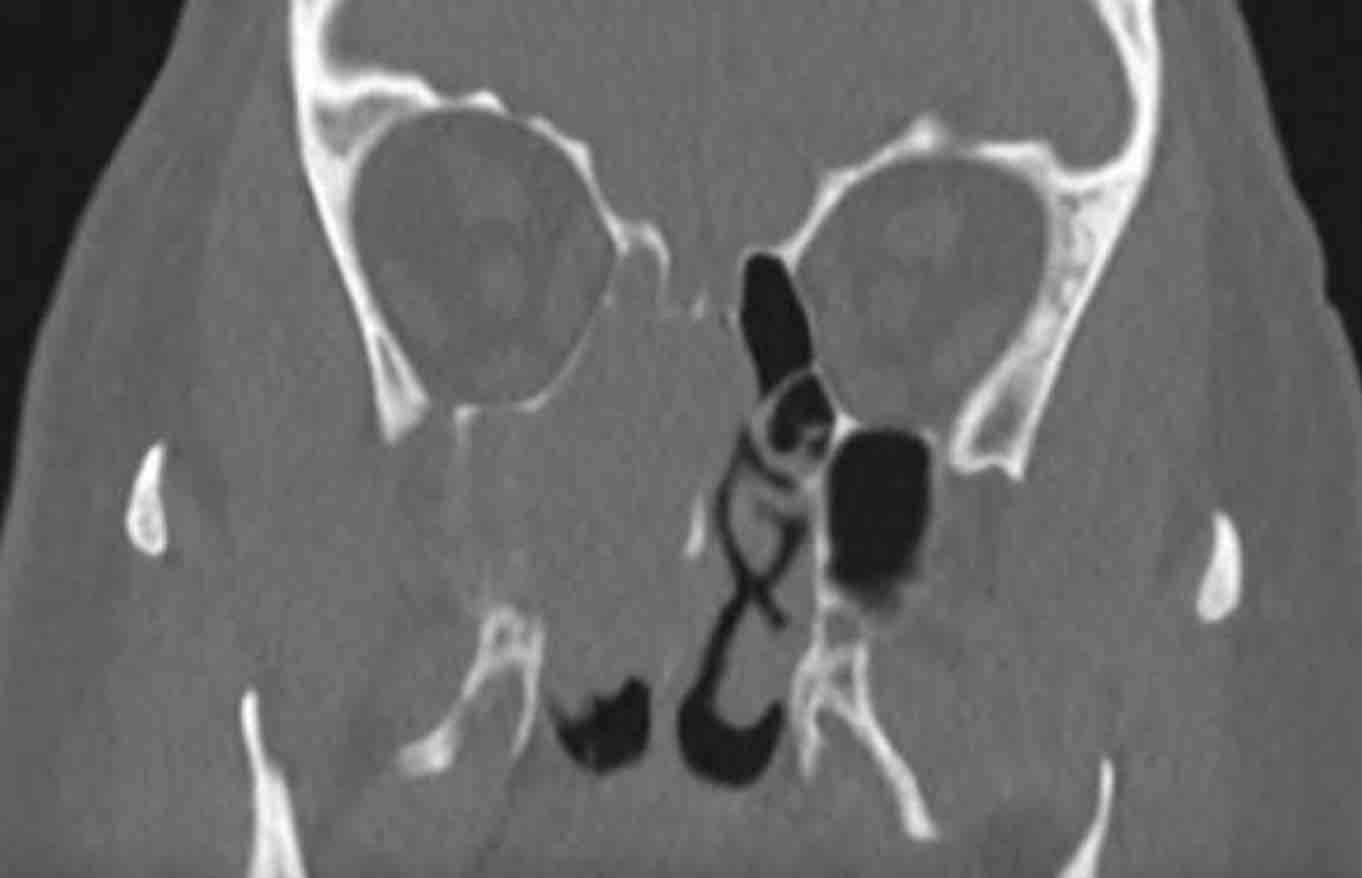

Các hình ảnh này của một bệnh nhân nam 16 tuổi với biểu hiện lồi mắt và chảy máu mũi.

Hãy quan sát kỹ các hình ảnh trước.

Tìm kiếm các dấu hiệu cảnh báo.

Sau đó tiếp tục đọc.

Dựa trên kết quả CT tại bệnh viện khác, có nghi ngờ u xơ mạch máu vị thành niên (juvenile angiofibroma) — một khối u tăng sinh mạch máu, xâm lấn tại chỗ, gặp ở nam giới trẻ tuổi với biểu hiện chảy máu mũi nặng, có thể đe dọa tính mạng.

Trên các hình ảnh này, có một tổn thương phá hủy xương với xâm lấn vào hốc mắt.

U xơ mạch máu vị thành niên luôn xuất phát từ hốc mũi phía sau và có tâm tổn thương xung quanh lỗ bướm khẩu cái và hố chân bướm khẩu cái.